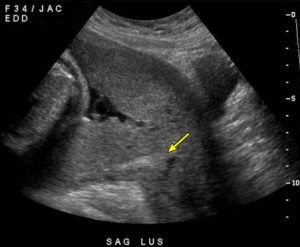

Rau bám thấp là gì? Những điều mẹ bầu cần biết để yên tâm hơn

Rau bám thấp là gì? Rau bám thấp là gì? Rau bám thấp là tình [...]

Rau bám thấp – Dấu hiệu, nguy cơ và cách theo dõi cho mẹ bầu

Rau bám thấp là gì? Rau bám thấp (low-lying placenta) là tình trạng bánh rau [...]